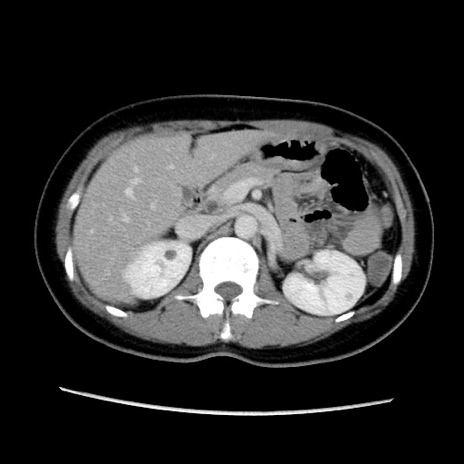

症例39(横断像)

【症例】40歳代女性

【主訴】上下腹部痛

【現病歴】2日目から下腹部痛あり。夜間は痛みで眠れなかった。昨日より上腹部痛と下痢が出現。臥位で痛みは軽快したため、休んでいた。本日になって臥位でも立位でも痛みが強くなってきたため救急要請。

【既往歴】子宮内膜症

【身体所見】部:平坦・軟、左上下腹部に圧痛あり、反跳痛あり。

【データ】WBC 21800、CRP 26.78